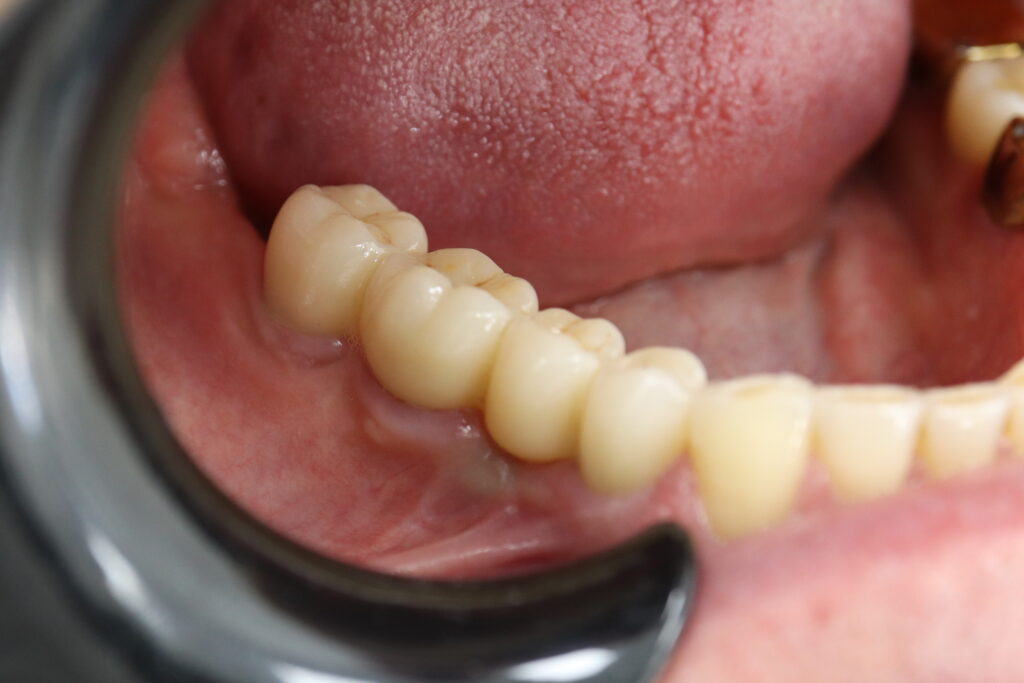

Также на нижнюю челюсть был изготовлен мостовидный протез из 4х коронок (цирконий) с опорой на 3 индивидуальных абатмента с одной стороны и 1 коронка на иплантат с другой.

Пациенту были установлены 6 имплантатов Megagen AnyOne по системе All-on-6 на верхней челюсти и 4 имплантата на нижней по классической двухэтапной методике.

Спустя 27 дней был зафиксирован протез с опопрой на дентальные имплантаты из диоксида циркония с каркасом из титана.